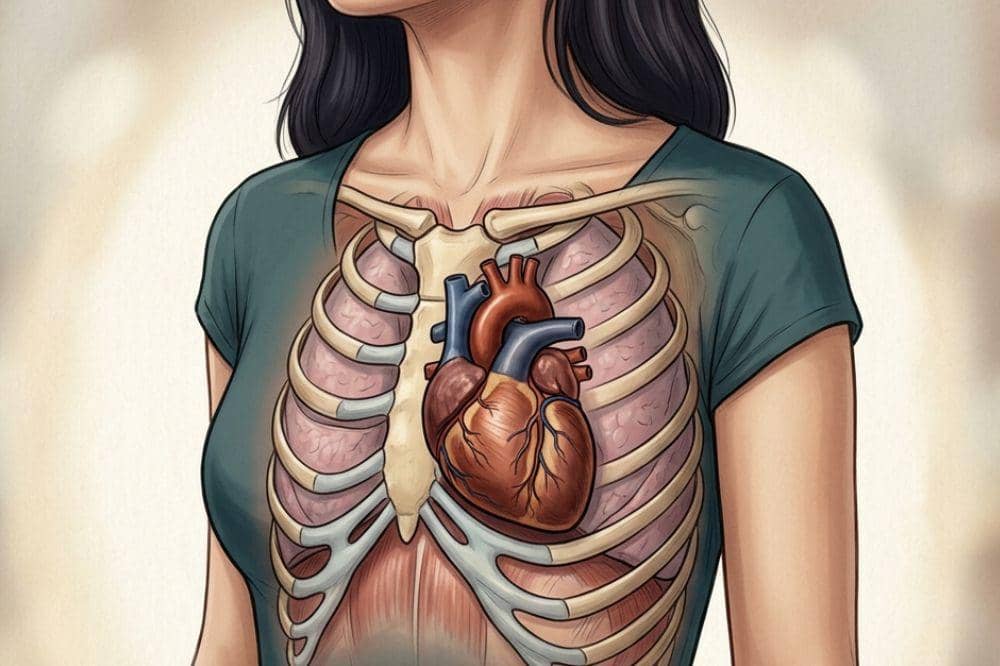

2. Jantung bekerja lebih keras hingga 40–50 persen

Selama kehamilan, jantung mama bekerja lebih keras dari biasanya karena harus memompa darah sekitar 40–50 persen lebih banyak untuk mendukung kebutuhan tubuh dan janin. Tidak hanya itu, detak jantung juga meningkat sekitar 10 hingga 20 kali per menit dibandingkan sebelum hamil.

Peningkatan kerja jantung ini bertujuan untuk mengalirkan lebih banyak darah ke plasenta dan tali pusar, sehingga janin mendapatkan oksigen dan nutrisi yang cukup untuk tumbuh dengan baik. Kondisi ini juga menjadi alasan mengapa Mama mungkin lebih cepat merasa lelah dibandingkan sebelum hamil, karena tubuh sedang bekerja ekstra untuk mendukung kehamilan.